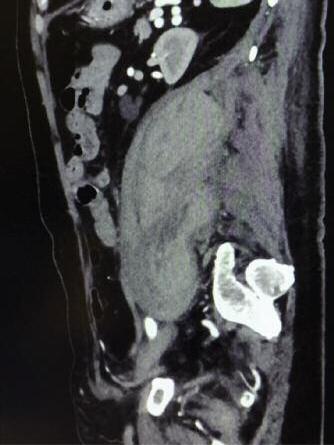

World Health Organization declared Coronavirus disease 2019 (COVID-19) a pandemic (3) and Italy was one of the country most severely involved by this new pathology. Given the fact that SARSCoV-2 has been correlated to an increased incidence of thromboembolic events such as catheter thrombosis, deep venous thrombosis, and pulmonary embolism, the Italian guidelines sugge- sted to evaluate the use of anticoagulant therapy, in particular LMWH 150 UI/kg in single administration to prevent trombo-embolic events (4) Retroperitoneal ematomas are a known complication of 0,5 – 1% patients undergoing systemic anticoagulation.(5) Moreover critical patients with Covid 19 frequently presents risk factors as thrombocytopenia, antiplatelet therapy, reduced func- tional capacity, diabetes, anemia, renal failure and liver failure

A critical 62 years old patient with no comorbidity stayed 21 days in ICU and was successfully weaned after 12 days of mechanical ventilation for pneumonia Covid 19 related. Central venous catheter was positioned in the first day of ICU. First day after weaning patient complained severe left flank radiated to

Corresponding author: Lt MD Martina Mariani, Italian Army, Policlinico Militare Celio, UOC Anestesia Rianimazione e Terapia del dolore, Rome, Italy E-mail: martina mariani@yahoo com leg pain with positive bloomberg sign, tachycardia 130 bpm, blood pressure was mainteined 125/80 Haemoglobyn weas falling gradually in the last 2 days from 10 5 mg/dl to 7 8 mg/dl Platelets dropped from 565 at admission to 167 the day before bleeding Medicaments administrated were: Enoxaparin 150 UI/kg for 13 days, Tocilizumab 600 mg for 2 days. A computed tomography scan was performed immediately and demonstrated a large left Ileo-psoas muscle hematomas (Fig.1). Selective arterial embolization were not performed because no signs of active bleeding were detected and conservative pathway with clinical monitoring was preferred. Enoxaparin was discontinued for 2 days and then re-administered 75 UI/kg 2 packed red blood cell were administrated during the length of stay in the intensive care Unit (ICU) No more episode of bleeding were recorded Patient was discharged from ICU 3 days after bleeding